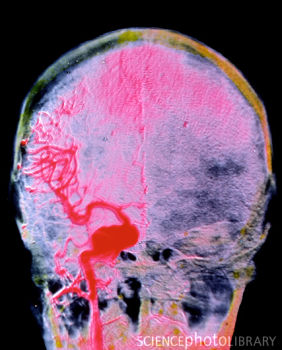

在美国,中风是造成病人残疾的第一诱因,还是第三大导致死亡的因素。近日,神经学家们发现一种调控神经细胞的蛋白可在病人中风后帮助维护大脑的正常功能,是防止长期损伤的关键因素。

Cypin蛋白可调控神经细胞与神经元分支的功能,对于维护正常的脑部功能至关重要。其可保护神经细胞在初次发生中风时不受损伤,维护其与其他细胞交流的正常能力,并阻止脑部和神经组织的再次受损。而PSD-95蛋白会加速细胞损伤及抑制恢复。中风的二次损伤通常发生在初次损伤的数天,甚至是数周内,它表现为血流量不足、供氧不足和脑部肿胀。